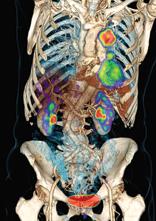

This is a lung cancer tumor radiotherapy treatment plan for the Accuray CyberKnife system demonstrated at the American ...